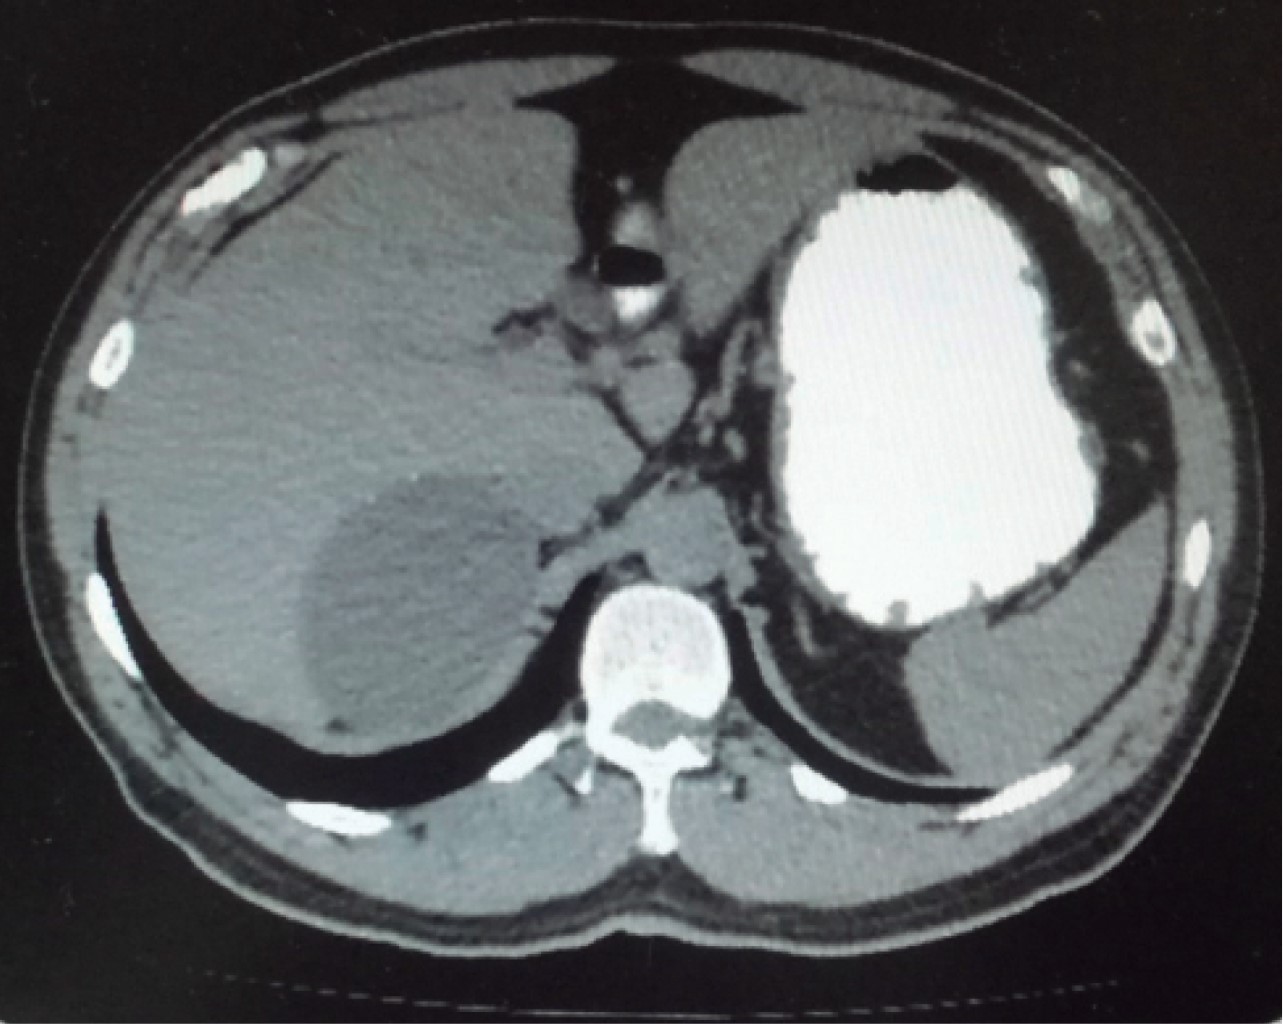

In May 2018 he had normal cytology blood cell counts, liver and renal function tests, and coagulation parameters. No cortisol, aldosterone, urinary catecholamine or metanephrine measurements were done. An abdominal CT scan performed in May reports a right adrenal gland hypodense image with a maximum diameter of 101 mm with calcification images inside it that was exerting occupational and compressive effect on surrounding structures (Figures 3, 4, 5 and 6). Once internal medicine service completed his preoperative assessment, an open anterior surgical approach was scheduled. He was given antibiotic prophylaxis with ceftriaxone 2 g in a single dose before a right subcostal incision was made and we proceeded to electrocautery removal of the right adrenal cyst of 10 × 9 cm. Adhesions to the liver were found and a content of approximately 400 ml of hyaline fluid and calcifications of about 20 × 40 mm in its interior were seen. A Penrose drainage of ½" (19 mm) was placed in the subphrenic space due to the suspicion of postoperative hemorrhage.

Figure 5

Figure 6